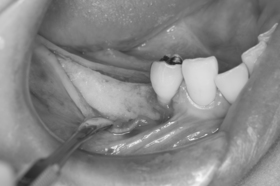

歯肉弁を剥離した状態です。

基底部から歯槽頂にかけて徐々に骨が薄く(細く)なっております。

大臼歯相当部に2本のインプラントを若干深めに埋入すると、第1大臼歯相当部のインプラント(フィクスチャー)の一部が、歯槽骨から露出しているのが確認できます。